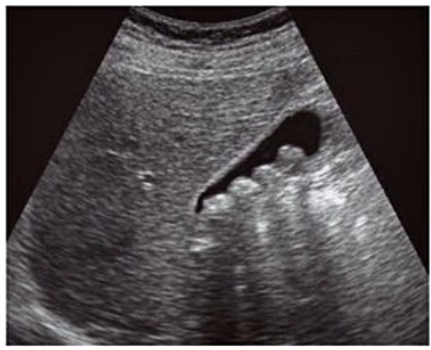

USG colelitíase

A

• método de escolha

• primeiro exame a ser solicitado

• achado característico é um ou mais focos hiperecogênicos móveis com sombra acústica dentro da vesícula biliar que se move de acordo com a posição do paciente

• visualiza também o espessamento da vesícula

qual o diagnóstico e o que é observado na imagem

• colelitíase

• cálculos alinhados dentro da vesícula

• sombra acústica